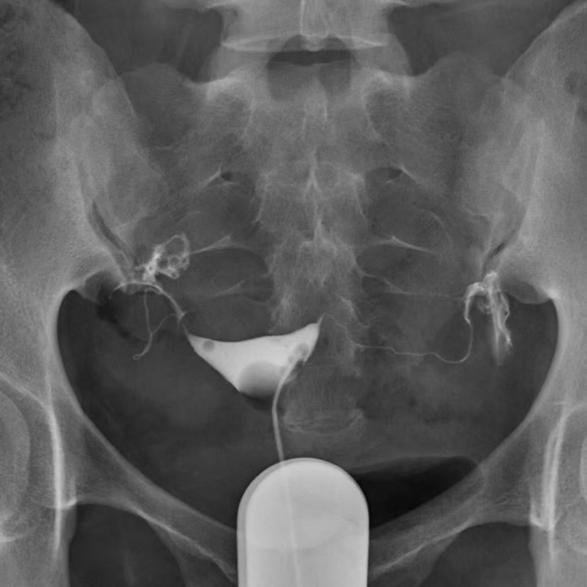

子宫输卵管造影是通过向宫腔及输卵管内注入造影剂,在X光透视下动态观察其流动与分布,从而评估子宫形态、输卵管通畅度及盆腔粘连情况的检查方法。它不仅能够判断输卵管是否通畅,还能间接评估其蠕动与拾卵功能,对发现宫腔病变、指导后续治疗具有重要意义。

传统子宫输卵管造影采用宫腔球囊造影管,需导管置入宫腔并充盈导管前端球囊。当有子宫发育畸形、子宫曲度大、宫腔广泛粘连、子宫颈病变时,会导致插管困难,增加生殖道损伤的风险,患者疼痛感比较强烈,图像上不利于观察子宫腔全貌;当球囊充盈过度时,还可能发生导管头端顶住宫角导致同侧输卵管近端梗阻的假阳性。

如今,随着技术进步,新型造影管(导管头端呈蘑菇头状)应运而生。它仅置于宫颈外口或宫颈管,无需进入宫腔,即可完成造影,真正实现无痛置管、全面显影。

管身在宫颈外口,造影过程中能观察子宫腔、输卵管的全貌。

传统球囊导管造影法

新型(蘑菇头)导管造影法